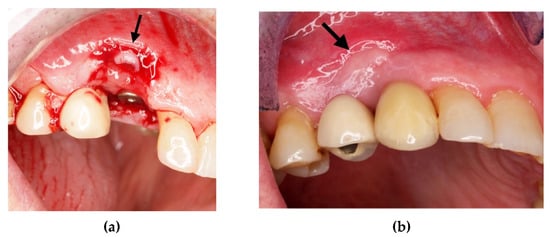

After three months, the foil was removed (Figure 21a,b) and the roots surface previously exposed, appeared covered by bone.

(a) Removal of sutures after 3 weeks; (b) extensive healing tissue is observed which has completely covered the previously exposed roots.

A Comparative radiological analysis before and after the surgical procedure, showed an increase in the distal bone peak. The gained bone was also maintained after 6 months of follow-up (Figure 22c). After one year (Figure 22d), the distal bone peak was comparable in height with the vestibular one.

(a) Initial periapical radiograph; (b) periapical radiograph after foil placement; (c) periapical radio-graph after 6 months; (d) periapical radiograph after one year.